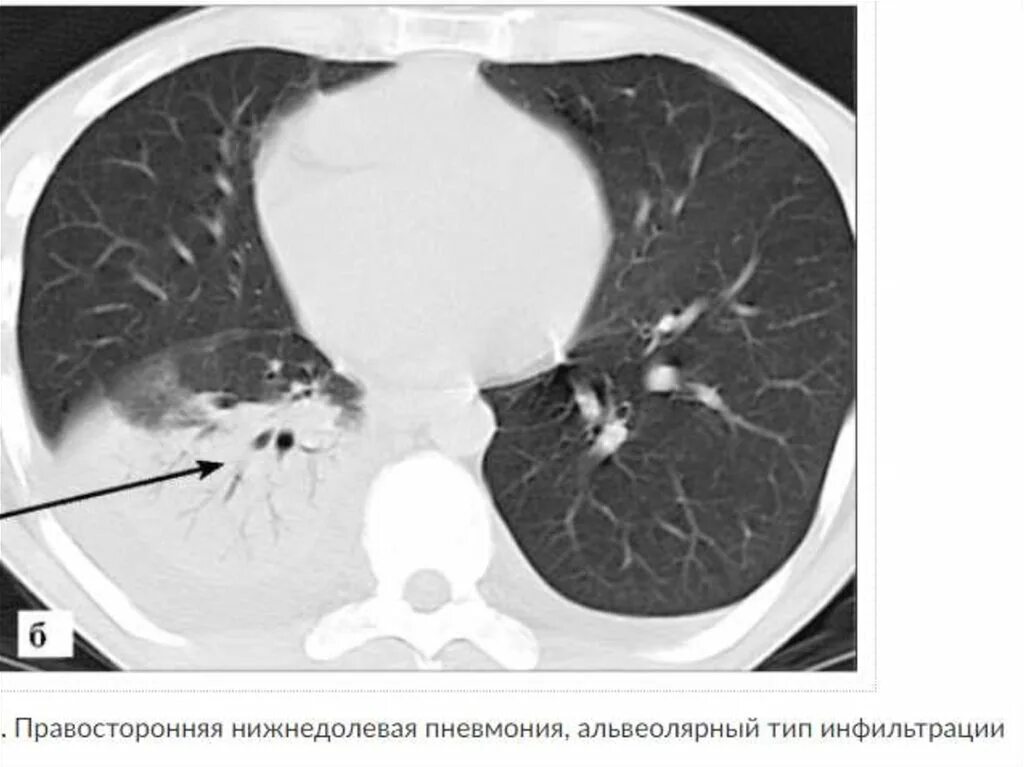

Как выглядит пневмония на кт